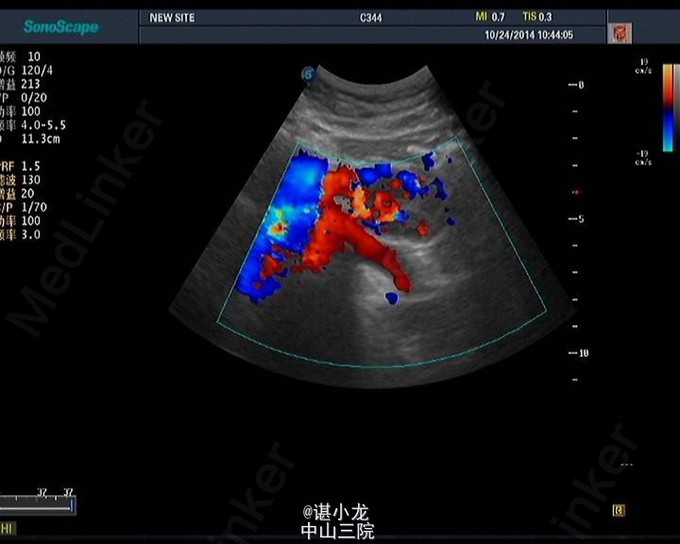

皮肤、巩膜无黄染,肝掌征阴性,未见蜘蛛痣,腹部外形平坦,腹部轻度彭隆,未见胃肠形或蠕动波,脐部未见异常,未见腹壁静脉曲张,腹部可见剖宫产手术瘢痕,全腹壁柔软,无波动感,全腹无压痛反跳痛,肝脏脾未及,肝区叩击痛阴性,移动性浊音阴性,肠鸣音正常,4-5次/分,振水音阴性,未闻及腹部血管杂音。 2014-10-22血常规:白细胞总数3.920x10E9/L,血小板计数199.000x10E9/L,血红蛋白浓度119.000g/L。生化全套:钾3.670mmol/L,钠141.700mmol/L,肌酐(酶法)66.000umol/L,糖4.710mmol/L,总胆红素9.740umol/L,白蛋白39.700g/L,谷丙转氨酶32.000U/L,谷草转氨酶22.000U/L。凝血四项:凝血酶时间18.300sec。 彩超肝胆脾胰+门静脉+腹部大血管见:胰腺体尾交界处、胰腺下方低回声团,性质待定,建议进一步检查。门静脉、肝静脉、下腔静脉血流通畅。心电图胸片未见异常。

诊断:腹膜后肿物 治疗:腹膜后肿物切除术 手术简要过程:麻醉成功后,取平卧位,术野皮肤常规消毒,铺巾;取左侧经腹直肌外缘切口,长约15cm ,逐次切开皮肤,皮下组织,电刀止血,电刀切开腹直肌和腹直肌前后鞘,切开腹膜;打开胃结肠韧带,探查见胰体尾部胰腺后方存在一约4*2cm大小实性肿物,与周围组织粘连,遂决定行腹膜后肿物切除术。分离肿物与周围粘连,暴露最低部位,在肿物最低处见多个动脉供应,沿着动脉解剖分离周围组织,见改血管丛由肠系膜根部发出。打开肠系膜,将血管与周围组织分离,并用4#将血管结扎切断。再次游离肿物,将肿物完整游离切下。之后将打开的肠系膜按原位缝合。检查无活动性出血后,彻底清洗腹腔。清点器械无误后逐层关腹。切除组织送病理。病理回报Castleman Disease。